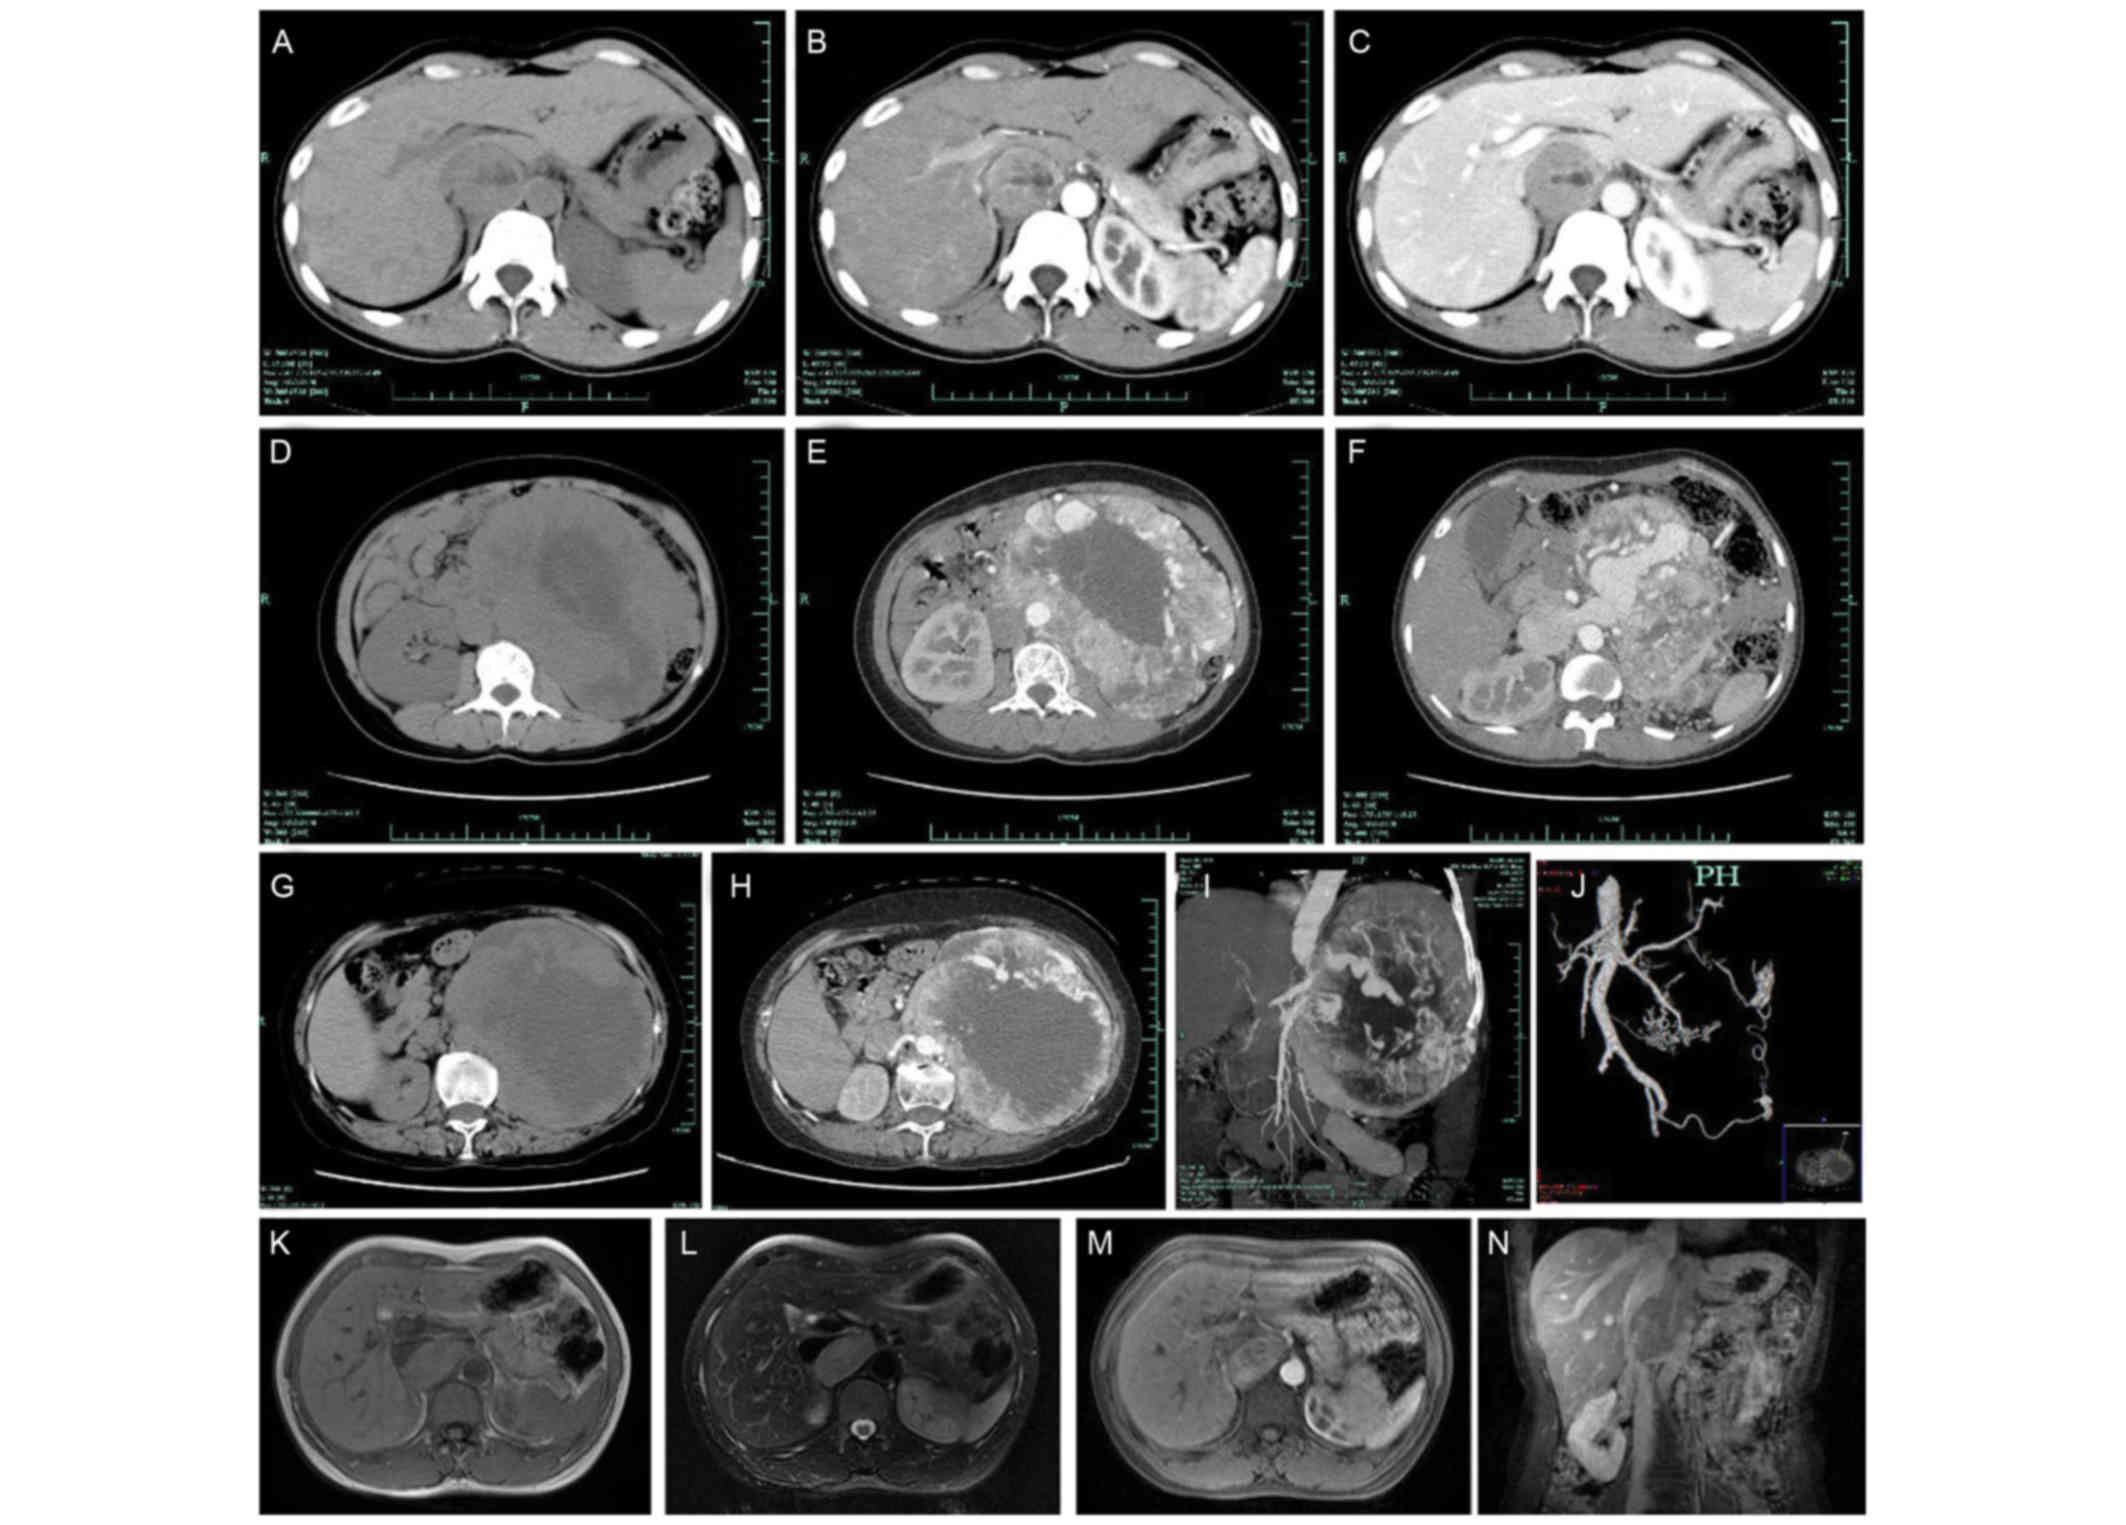

As presented in Fig. 1, all the patients underwent CT scans, which revealed retroperitoneal soft tissue masses, including homogeneous masses in 12 cases and inhomogeneous masses with cystic changes in 22 cases. Of the 34 patients, 20 patients exhibited strong enhancement with an increase in the maximum CT value >30 Hounsfield units (HU). A total of 10 cases exhibited mild to moderate enhancement which primarily occurred in the arterial phase (Fig. 1B, C, E, F and H). Thick and tortuous arteries and veins were observed in 4 cases, inside or at the periphery of the tumor (Fig. 1E, F, H-J). The structures of the tumors and surrounding tissues were clearly observed on preoperative CT scans of all patients.

Figure 1.

Representative radiological images of retroperitoneal paragangliomas. (A) CT image of patient no. 11; (B) CT image of patient no. 11; and (C) CT image of patient no. 11 which demonstrate a round demarcated soft tissue mass with cystic degeneration. The inferior vena cava was depressed by the mass and migrated laterally. The parenchyma of the mass exhibited enhancement, primarily in the arterial phase. (D) CT image of patient no. 10; (E) CT image of patient no. 10; and (F) CT image of patient no. 10, revealing a large oval retroperitoneal mass with cystic degeneration. The parenchyma of the mass exhibited enhancement, and thick tortuous arteries and veins were observed inside the tumor. The juncture point where the tumor vein joined the inferior vena cava was observed. (G) CT image of patient no. 24; (H) CT image of patient no. 24; (I) CT image of patient no. 24; and (J) CT image of patient no. 24, demonstrating a high oval retroperitoneal cystic mass on the left. The parenchyma of the mass exhibited enhancement, and thick tortuous arteries and veins were observed inside the tumor. The tumor arteries originated from the spleen artery, left renal artery, abdominal aortic artery and left internal iliac artery. (K) MRI image of patient no. 20; (L) MRI image of patient no. 20; (M) MRI image of patient no. 20; and (N) MRI image of patient no. 20, demonstrating an oval soft tissue mass posterior to the inferior vena cava. The mass exhibited equal intensities on T1WI and T2WI, and cystic degeneration was observed inside the mass. The mass exhibited an enhancement. The vena cava arched and became thin due to the tumor compression. CT, computed tomography; MRI, magnetic resonance imaging; T1WI, T1-weighted image; T2WI, T2-weighted image.

Masses were correctly localized to be retroperitoneal in 32 cases and were incorrectly localized to be intra-abdominal in 2 cases (Table II). All tumors were diagnosed using contrast-enhanced CT. Between November 1999 and December 2009, 3 cases were correctly diagnosed as retroperitoneal paragangliomas, 9 cases were diagnosed as retroperitoneal tumors (without diagnosis of a specific tumor) and 8 cases were misdiagnosed, as fibrosarcoma (n=2), stromal tumor (n=2), lymph node metastasis (n=1), leiomyoma (n=1), vascular tumor (n=1) and neurofibroma (n=1). Between January 2010 and December 2015, 8 cases were correctly diagnosed as retroperitoneal paragangliomas, 4 cases were diagnosed as retroperitoneal tumors (without diagnosis of a specific tumor) and 2 cases were misdiagnosed, as teratoma (n=1) and small intestinal lymphoma (n=1). The CT diagnostic accuracy between2000 and 2015 was significantly increased compared with that between 1999 and 2009 (P=0.014, z=−2.454).

A total of 7 patients underwent magnetic resonance imaging (MRI). The parenchyma of the tumors revealed equal intensities on T1-weighted imaging (T1WI) and T2-weighted imaging (T2WI) (Fig. 1K and L). In all 7 cases, cystic degeneration and necrosis with short T1 and long T2 signals were observed inside the tumor. In 3 cases, an enhanced MRI identified an enhancement in the tumor parenchyma, especially in the arterial phase (Fig. 1M and N). For all 7 cases, the structure of the tumors and the surrounding tissues were clearly observed on preoperative MRI scans. Masses were correctly localized to be retroperitoneal in all 7 cases; however, only 2 masses were correctly diagnosed as retroperitoneal paragangliomas. For the other 5 cases, the tumors were not specifically diagnosed.